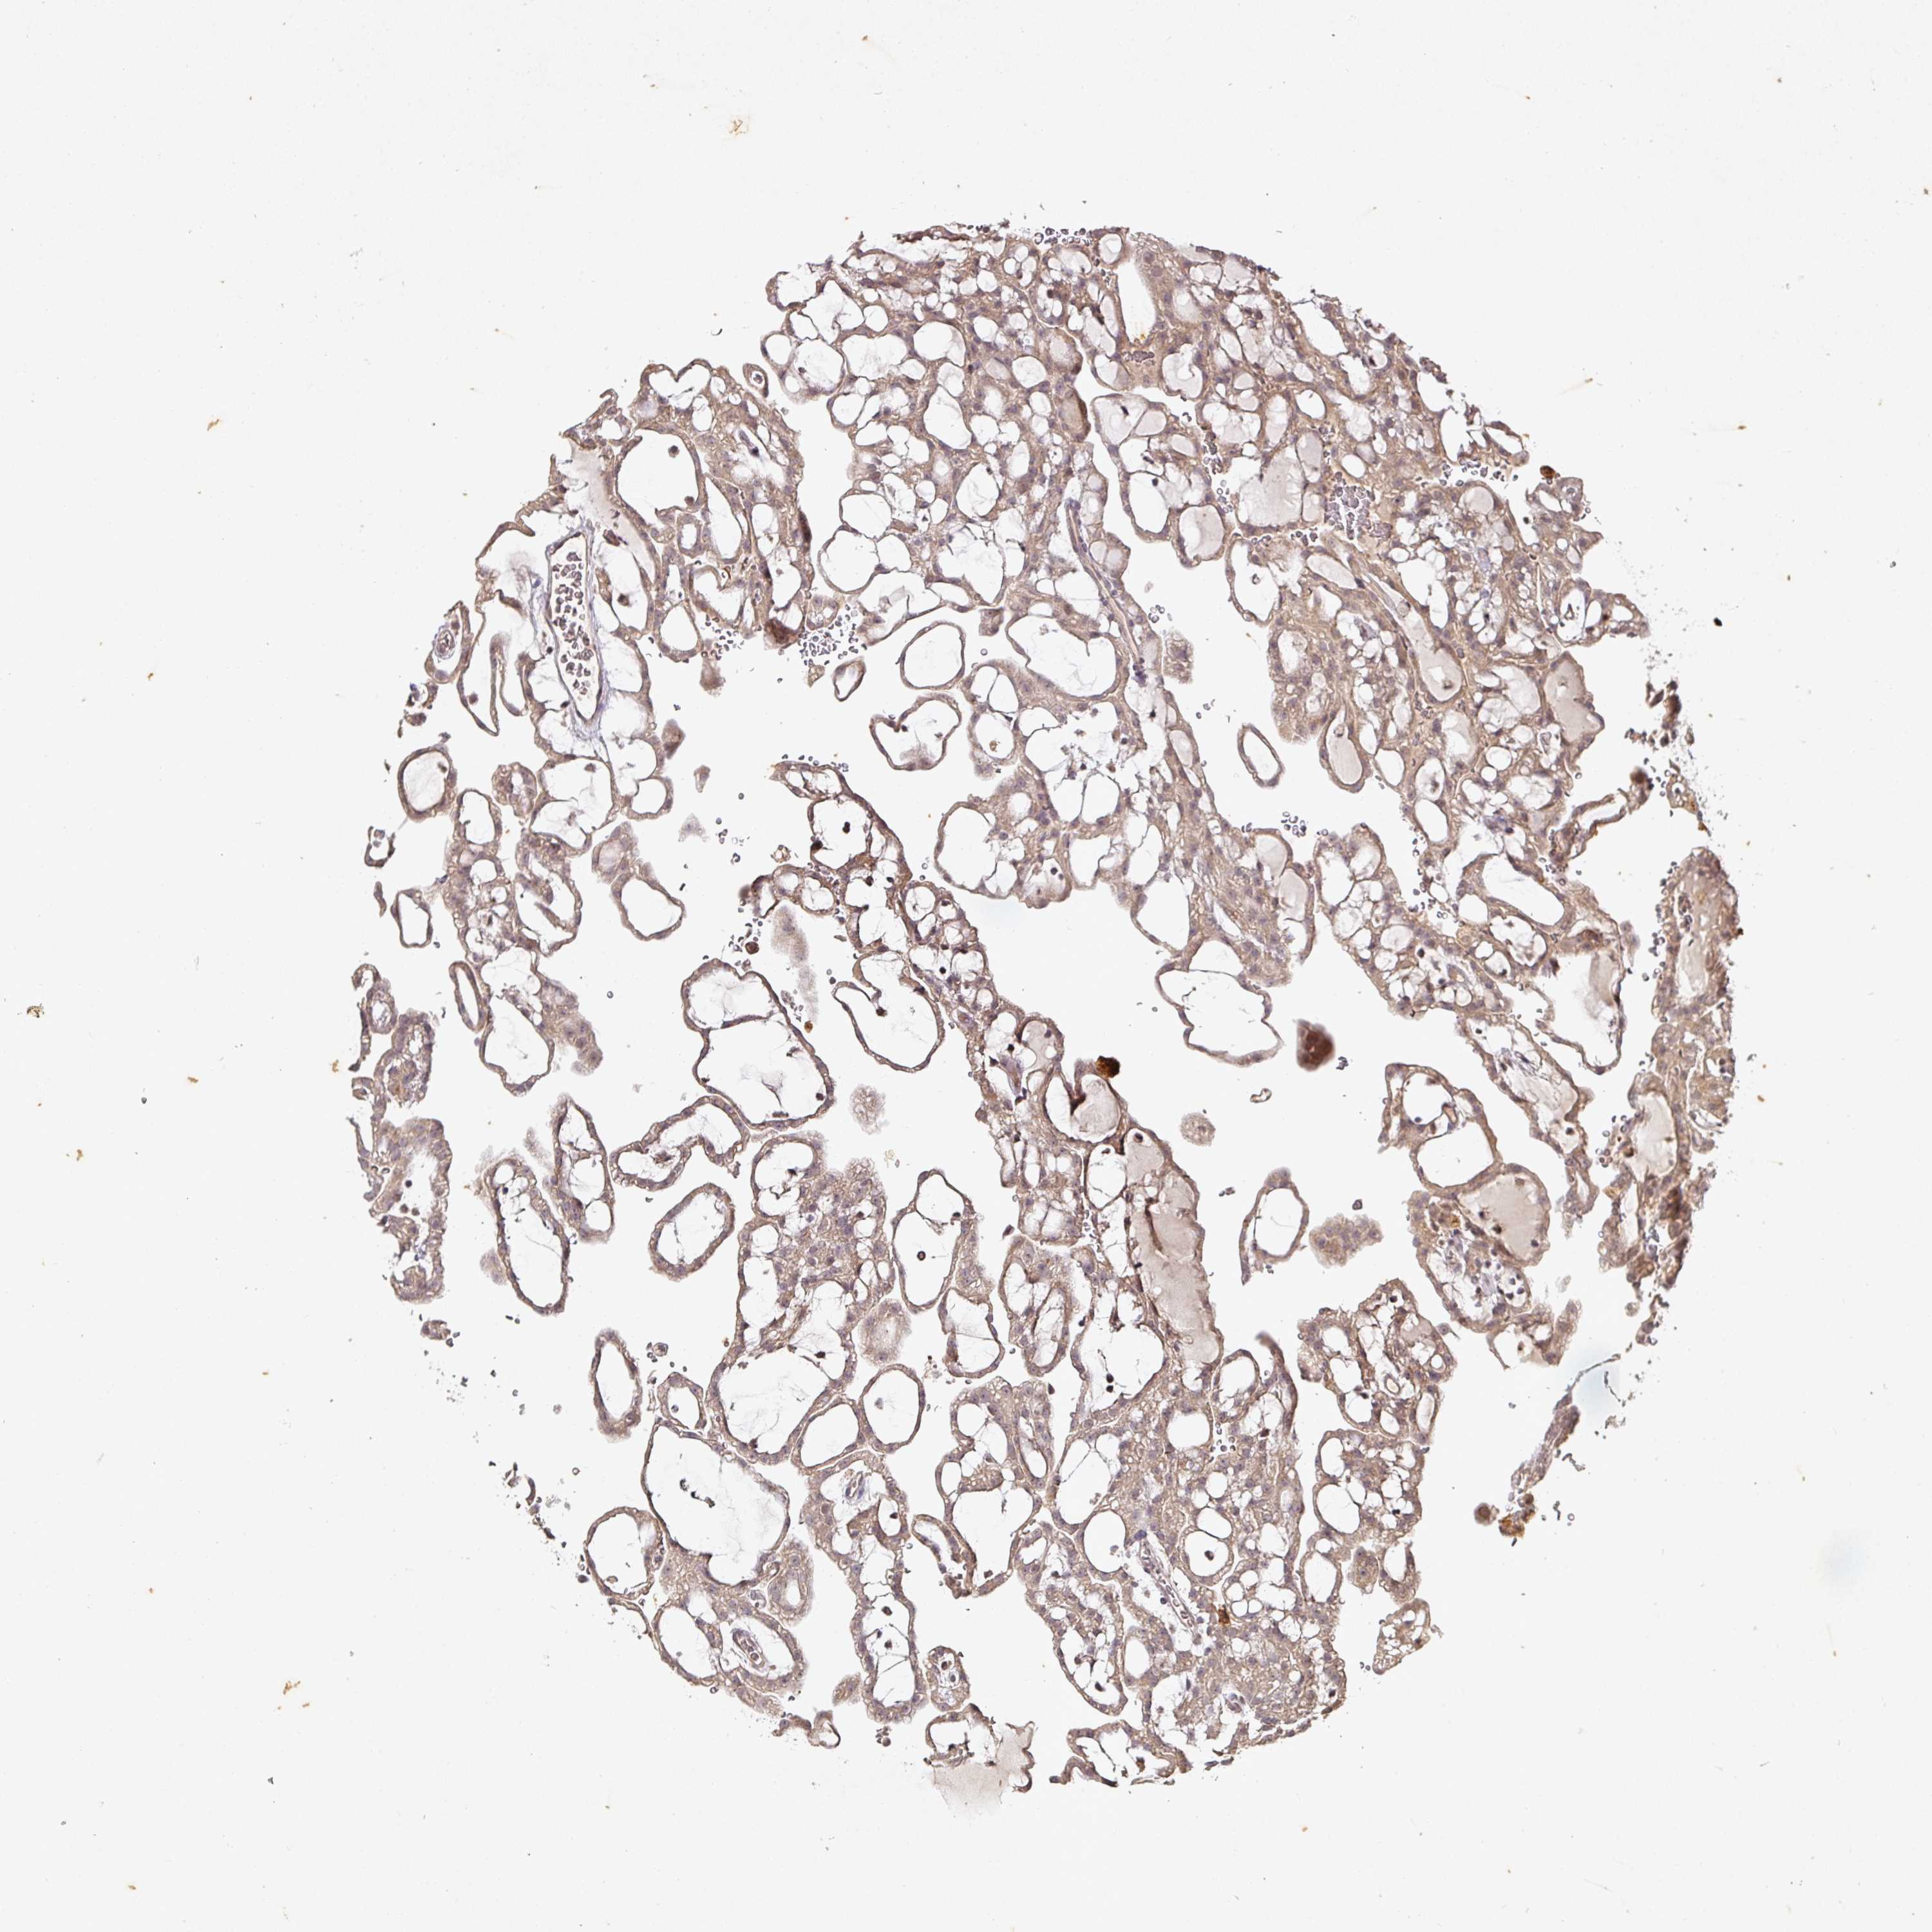

KIDNEY RENAL CLEAR CELL CARCINOMA (VALIDATION) - Interactive survival scatter ploti

The Survival Scatter plot shows the clinical status (i.e. dead or alive) for all individuals in the patient cohort, based on the same data that underlies the corresponding Kaplan-Meier plots. Patients that are alive at last time for follow-up are shown in blue and patients who have died during the study are shown in red.

The x-axis shows the expression levels (FPKM) of the investigated gene in the tumor tissue at the time of diagnosis. The y-axis shows the follow-up time after diagnosis (years). Both axes are complimented with kernel density curves demonstrating the data density over the axes. The top density plot shows the expression levels (FPKM) distribution among dead (red) and alive patients (blue). The right density plot shows the data density of the survived years of dead patients with high and low expression levels respectively, stratified using the cutoff indicated by the vertical dashed line through the Survival Scatter plot. This cutoff is automatically defined based on the FPKM cutoff that minimizes the p-score. The cutoff can be changed by dragging the vertical line or by entering a cutoff value in the square labeled "Current cut-off".

Under the Survival Scatter plot the p-score landscape (black curve; left axis) is shown together with dead median separation (red curve; right axis). Dead median separation is the difference in median mRNA expression between patients who have died with high and low expression, respectively. It is calculated as follows: median FPKM expression of dead patients with high expression - median FPKM expression of dead patients with low expression. This is intended to aid the user in visually exploring custom cutoffs and the associated p-scores and dead median separation.

Individual patient data is displayed and can be filtered by clicking on one or more of the category buttons on the top of the page. Categories describing expression level and patient information include: high, low, alive, dead, female, male and tumor stages. The scale of the x-axis can be toggled between linear and log-scale by clicking on the "x log" button. Mouse-over function shows TCGA ID, patient information and mRNA expression (FPKM) for each patient.

& Survival analysisi

Kaplan-Meier plots summarize results from analysis of correlation between mRNA expression level and patient survival. Patients were divided based on level of expression into one of the two groups "low" (under cut off) or "high" (over cut off). X-axis shows time for survival (years) and y-axis shows the probability of survival, where 1.0 corresponds to 100 percent.

CAPN5 is not prognostic in Kidney Renal Clear Cell Carcinoma (validation)

Best expression cut offi

Based on the FPKM value of each gene, patients were classified into two groups and association between prognosis (survival) and gene expression (FPKM) was examined. The best expression cut-off refers the FPKM value that yields maximal difference with regard to survival between the two groups at the lowest log-rank P-value. Best expression cut-off was selected based on survival analysis .

When clicking on this number, the vertical dashed line indicating cut-off, the interactive survival plot, and the Kaplan-Meier curve will be adjusted to show results based on the best expression cut-off.

: 11.14

P scorei

Log-rank P value for Kaplan-Meier plot showing results from analysis of correlation between mRNA expression level and patient survival.

N/A

TCGA RNA samplesi

RNA-seq data is reported as average FPKM (number Fragments Per Kilobase of exon per Million reads), generated by the The Cancer Genome Atlas (TCGA) .

Normal distribution across the dataset is visualized with box plots, shown as median and 25th and 75th percentiles. Points are displayed as outliers if they are above or below 1.5 times the interquartile range. FPKM values of the individual samples are presented next to the box plot.

Average pTPM 9.8

Number of samples 100